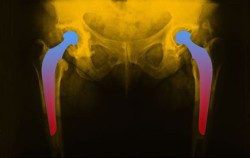

hip-implant-imageHip replacement surgery has improved the quality of life for millions of patients suffering from arthritis or hip fractures.

Yet, hip implants do not come without risks or hip replacement complications. In fact, patients implanted with certain metal-on-metal hip replacement systems may face an increased risk of hip dislocation.

Metal-on-Metal total hip replacement systems are made of a chromium-cobalt alloy and consist of a metal ball (femoral head), a metal femoral stem in the thighbone, and a metal cup in the hip bone (acetabular component).